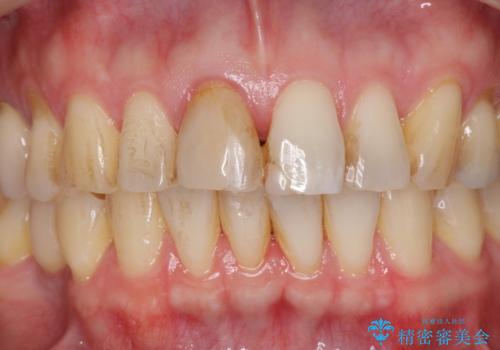

前歯の変色を改善 オールセラミック治療

- 目立つ前歯の変色の改善を希望され来院されました。

根管治療を行いそのままにしていると歯は、徐々に変色を来します。

感染の疑われる根管内に対し再度根管治療を行い、セラミッククラウンを作製することで審美性の回復します。